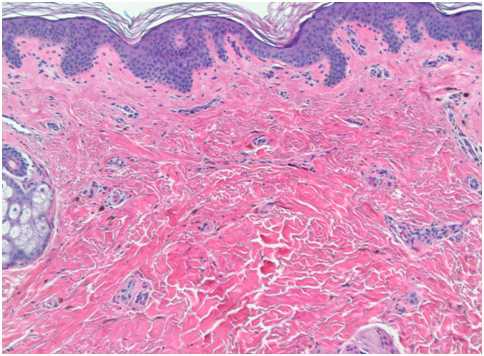

При гистологическом исследовании монгольских пятен видны сильно разветвленные меланоциты, которые располагаются в глубокой ретикулярной дерме и несут в себе много пигментированных меланосом (рис. 1). Как правило, меланоциты ориентированы параллельно эпидермису.

Рис. 1. Гистологические изменения в монгольском пятне (Dermpedia)